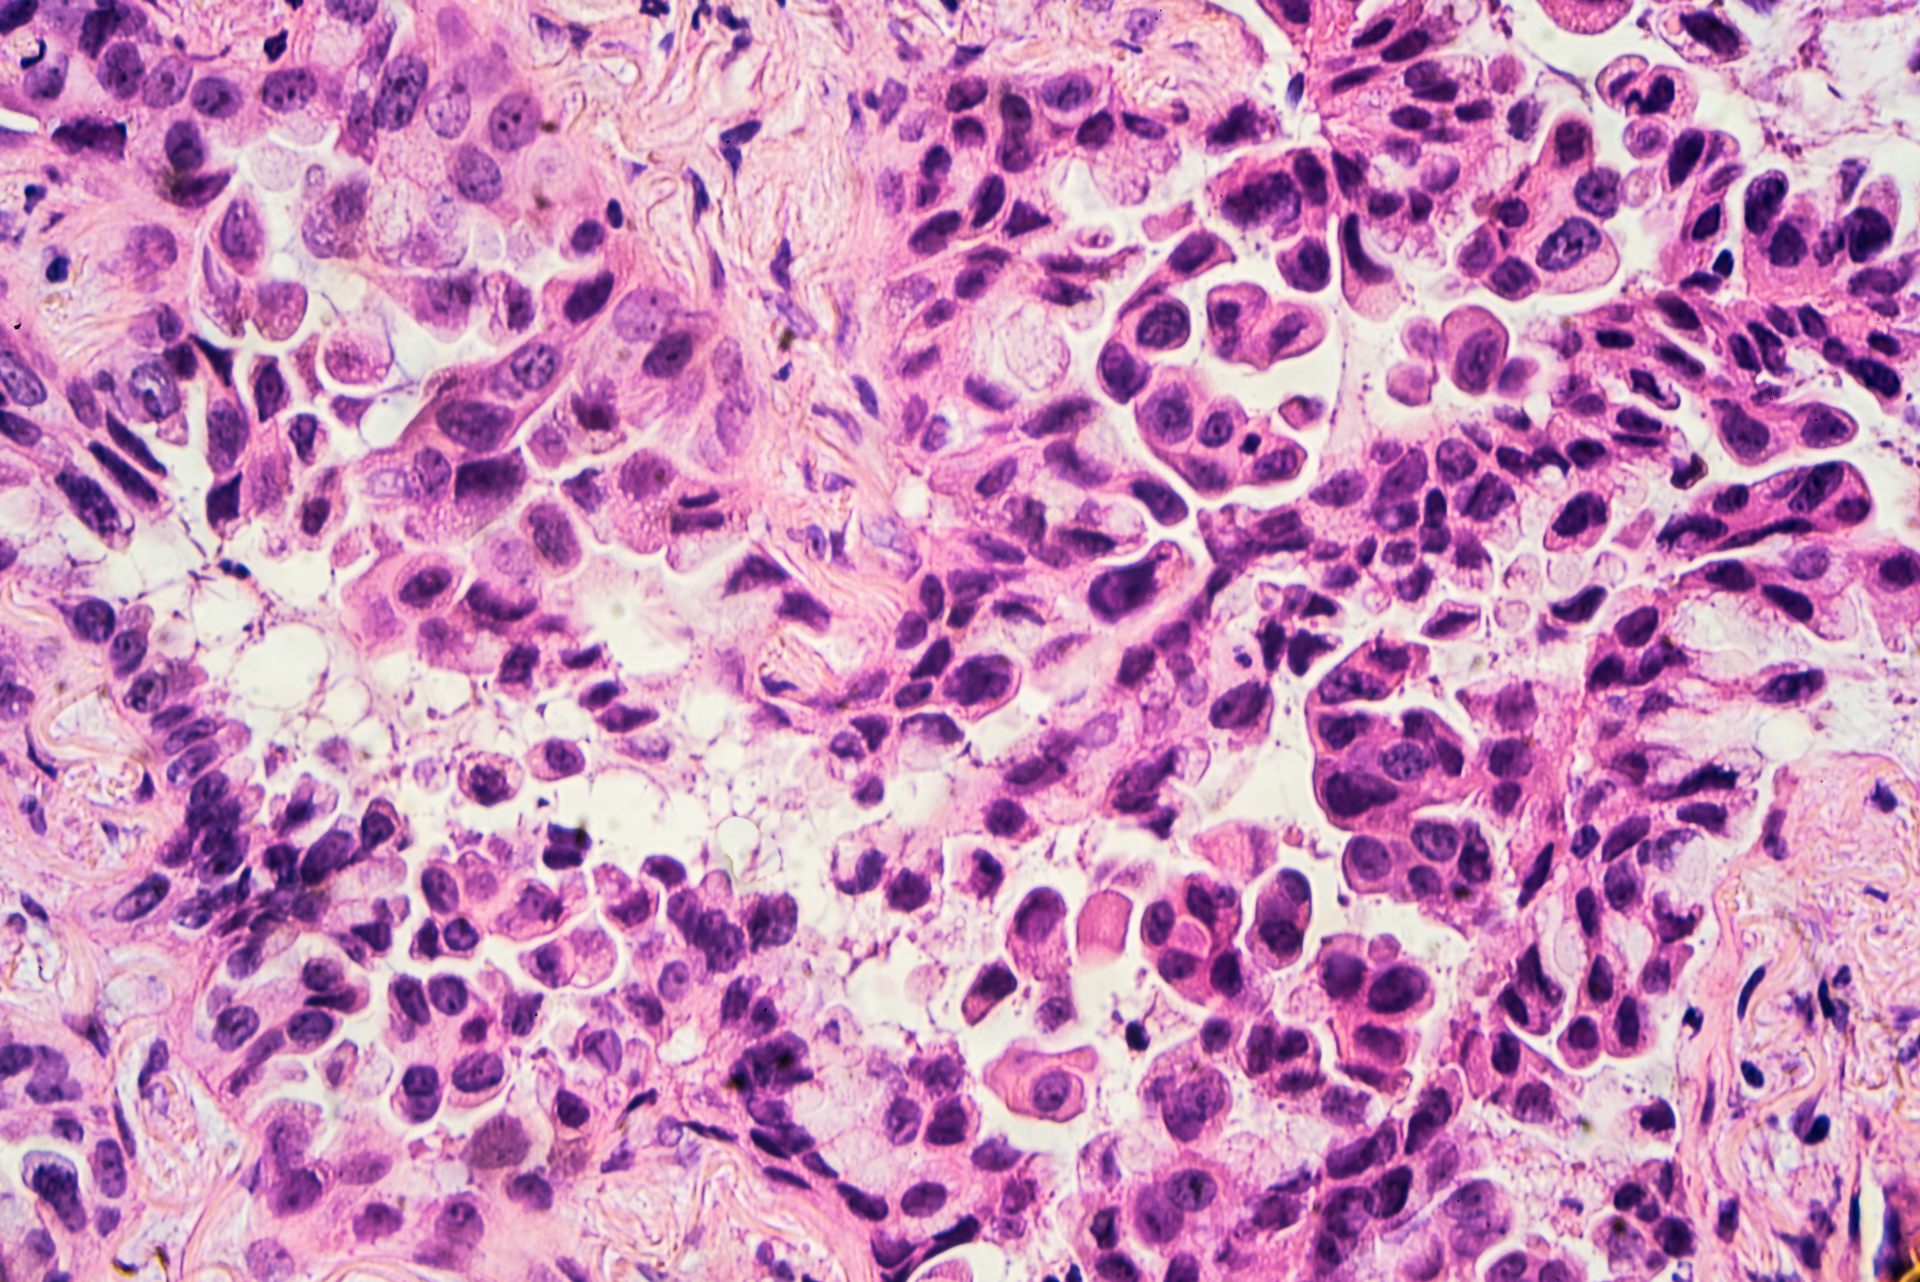

На фото: умеренно дифференцированная аденокарцинома матки

- Среднедифференцировання аденокарцинома матки представляет из себя полиморфные клетки, которые отличны от нормальных, имеют увеличенное гиперхромное ядро и ядрышки, могут наблюдаться патологические митозы.